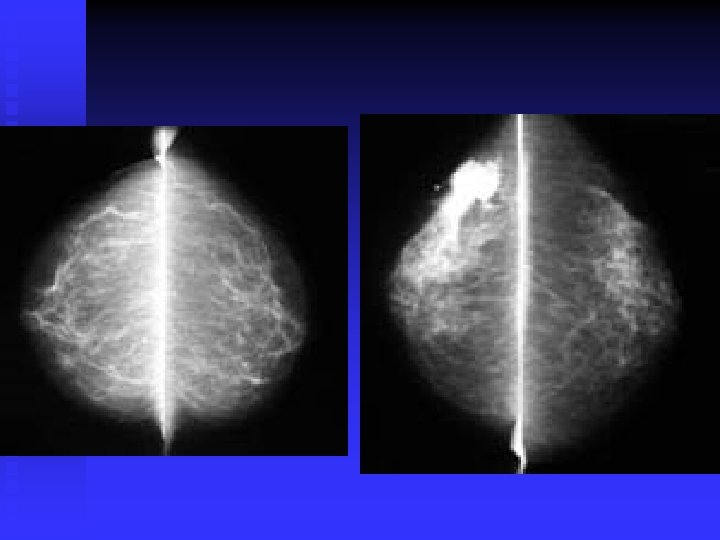

Infiltrating Ductal Cancer